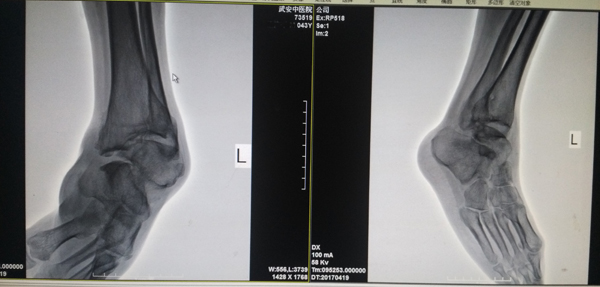

術(shù)湔

近日,患者到武安市中醫(yī)院進(jìn)行治療。檢驗(yàn)顯示:左踝關(guān)節(jié)形成創(chuàng)傷性關(guān)節(jié)炎,外翻明顯畸形伴有踝關(guān)節(jié)半脫位,距骨脫出,診斷為比較嚴(yán)重的創(chuàng)傷性踝關(guān)節(jié)炎。此種病例的最佳治療方式是進(jìn)行踝關(guān)節(jié)融合術(shù)。于是,骨傷二科醫(yī)生向家屬介紹了病情和手術(shù)的利弊,在征得患者家屬同意后為患者實(shí)施手術(shù)。為了保證質(zhì)量,術(shù)前經(jīng)過(guò)反復(fù)討論,制定了詳細(xì)周密的治療方案,而后,在麻醉科的全力配合下,對(duì)患者如期進(jìn)行了手術(shù)。術(shù)中他們采取前側(cè)口及后縱切口聯(lián)合切口,充分暴露踝關(guān)節(jié)及距骨,將踝穴及距骨做恰當(dāng)?shù)奶幚砗,使距骨充分?fù)位與踝穴對(duì)應(yīng),保持踝關(guān)節(jié)90度位,應(yīng)用鈦扳加以固定,鈦針輔以固定,手術(shù)順利完成。